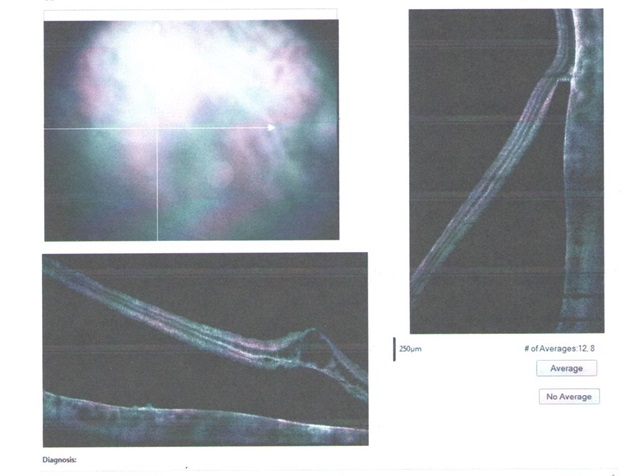

4. Optical coherent tomography — we obtain linear retinal sections to determine the anatomical parameters of the smallest sections in the central and close to it areas. The result may be a two- or three-dimensional image.

4.光学相干断层扫描-我们获得线性视网膜切片,以确定中央区域及其附近区域中最小切片的解剖学参数。 结果可以是二维或三维图像。